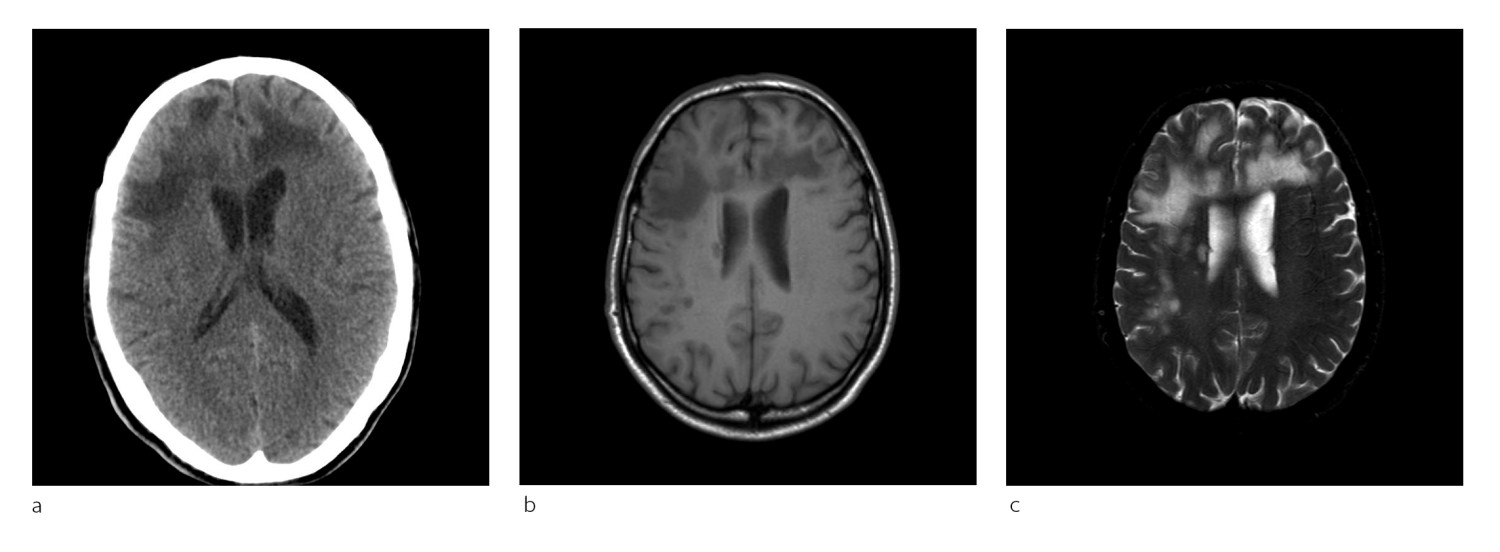

Pasient 2. En kvinne i 50-årene med attakkpreget multippel sklerose var blitt behandlet med natalizumab (Tysabri) over flere år da hun fikk påvist diskrete forandringer på en MR-undersøkelse. Hun hadde da ikke hatt tegn til sykdomsaktivitet på flere år. JCV-antistoff var blitt påvist i serum to år tidligere, men indeks var ikke tilgjengelig på dette tidspunktet. Natalizumab ble seponert, men pasienten utviklet etter hvert likevel ustøhet og dobbeltsyn, og MR-undersøkelse to måneder senere viste betydelig økning av forandringer (fig 2a). Det var en inhomogen høyattenuerende forandring i høyre lillehjernestilk som ikke er lett å skille fra en forandringer ved multippel sklerose. PCR-undersøkelse av JCV-DNA avdekket 1 173 kopier/ml i spinalvæske.

Plasmaferesebehandling ble gitt, men symptomene progredierte. Ny MR-undersøkelse tre uker senere viste kontrastladende lesjoner, forenlig med immunrekonstitusjonsinflammasjonssyndrom (fig 2b). Pasienten fikk høydose metylprednisolon (Solu-medrol), med påfølgende remisjon. Hun ble frisk fra progredierende multifokal leukoencefalopati, men fikk sekvele.

Ved mistanke om progredierende multifokal leukoencafalopati skal det gjennomføres MR-undersøkelse. Forandringer kan ses i hjernens hvite substans som multiple små lesjoner og/eller større konfluerende områder hvor som helst i storehjernen, oftest subkortikalt (fig 1), og i lillehjerne og hjernestamme (fig 3). Signalforandringer i ryggmargen bør gi mistanke om annen lidelse, men kan angivelig forekomme ved progredierende multifokal leukoencafalopati, men svært sjelden (20). Normale MR-bilder utelukker vanligvis tilstanden, men ved vedvarende klinisk mistanke bør undersøkelsen gjentas.

Diagnostikken kan være utfordrende hos pasienter med multippel sklerose, da grunnsykdommen i seg selv gir varierende nevrologisk utfall og multiple lesjoner i hvit substans, og den lar seg ikke uten videre skille radiologisk fra progredierende multifokal leukoencafalopati. MR-undersøkelse før oppstart med immunmodulerende behandling for senere sammenligninger er derfor viktig. Det ses ingen eller kun minimal masseeffekt, og vanligvis er det ikke eller kun beskjedent kontrastopptak.

Dersom det er kontrastopptak i en lesjon ved progredierende multifokal leukoencafalopati, indikerer det sterkt at det foreligger immunrekonstitusjonsinflammasjonssyndrom (IRIS) (fig 2). Dette ses relativt ofte ved både natalizumab- og hivassosiert infeksjon. En halvmåneformet cerebellær lesjon ses nesten utelukkende ved progredierende multifokal leukoencafalopati (fig 3) (20). De viktigste differensialdiagnosene inkluderer multippel sklerose, hivencefalitt eller eventuelt andre encefalitter (herpes simplex-virus, cytomegalovirus), gliomatosis cerebri, lymfom i sentralnervesystemet, akutt disseminert encefalomyelitt (ADEM), vaskulitter/cerebrale infarkter og mitokondriecytopatier (20).